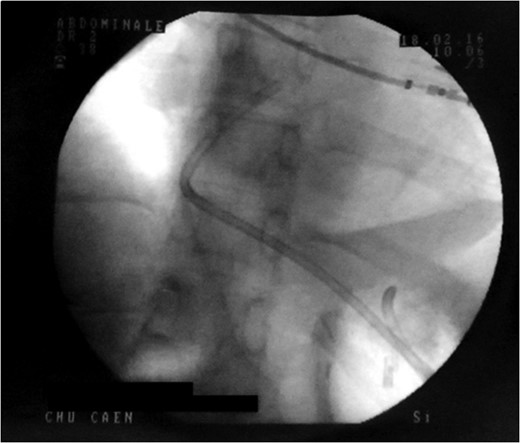

Control X-ray after the double pigtailed drain has been put up.